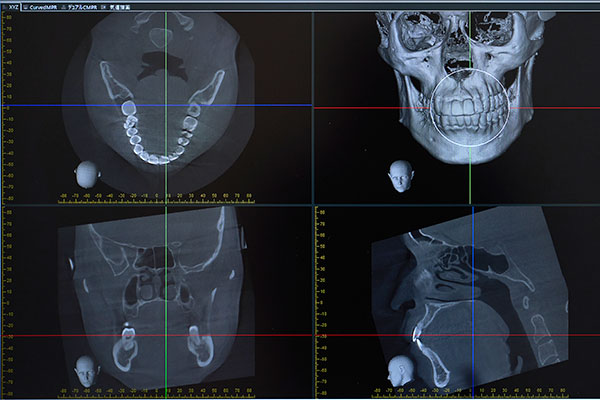

精密な診断と治療計画

安全かつ確実なインプラント治療には、精密な診断が不可欠です。当院では、血管や神経の位置を三次元的に観察でき、あごの骨の量や密度などの詳細を把握できる歯科用CTを使用します。このCTで得られたデータに基づき、専用のソフト上でインプラントの埋入位置や角度、深さをシミュレーションすることができます。これにより、術前にすべてを予測し、リスクを最小限に抑えた精密な治療計画を立案します。

精密検査

歯科用CTによる撮影など精密な検査を行い、あごの骨の状態や神経・血管の位置を正確に把握するための詳細なデータを取得します。これらのデータを用いて事前シミュレーションのもと、治療計画を作成します。